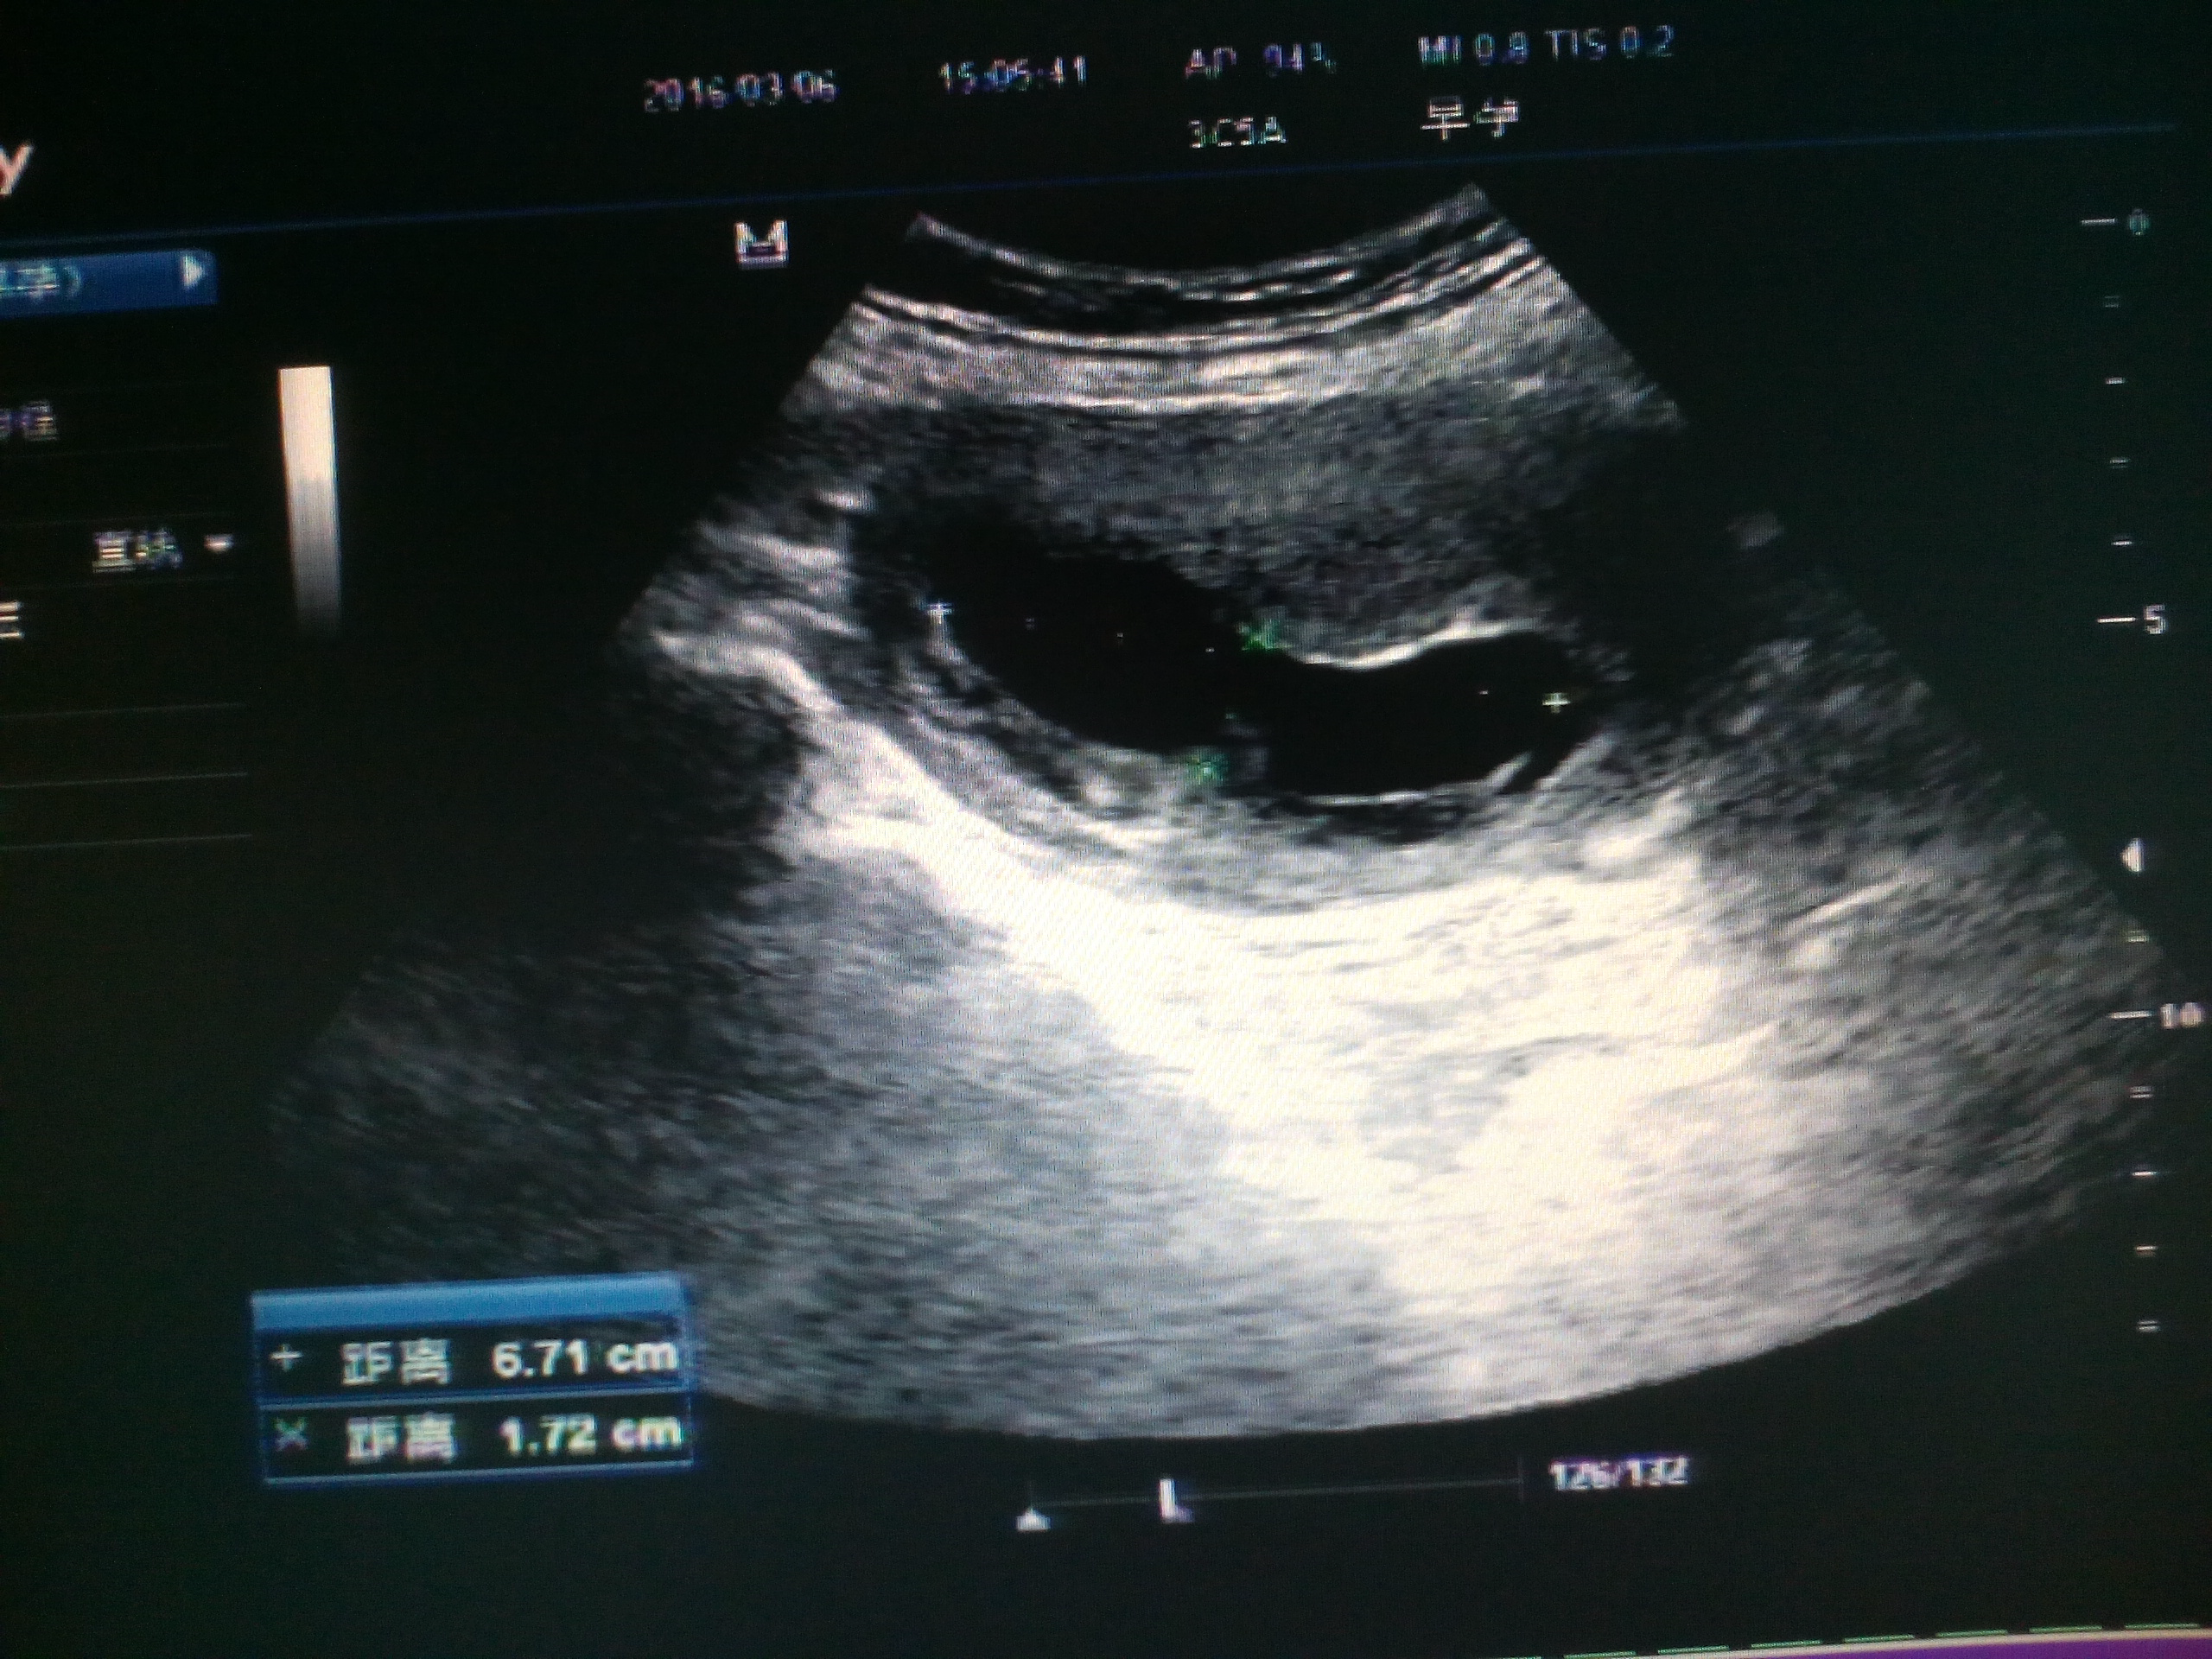

不完全性葡萄胎

病人,女42y,停经有三月余,主诉有断断续续出血为黑色,***检查,孕囊平均经大小约42mm,内见胚芽长约25mm,未见心血管搏动,图如下 CDFI:后壁见丰富得血流信号,胎盘?